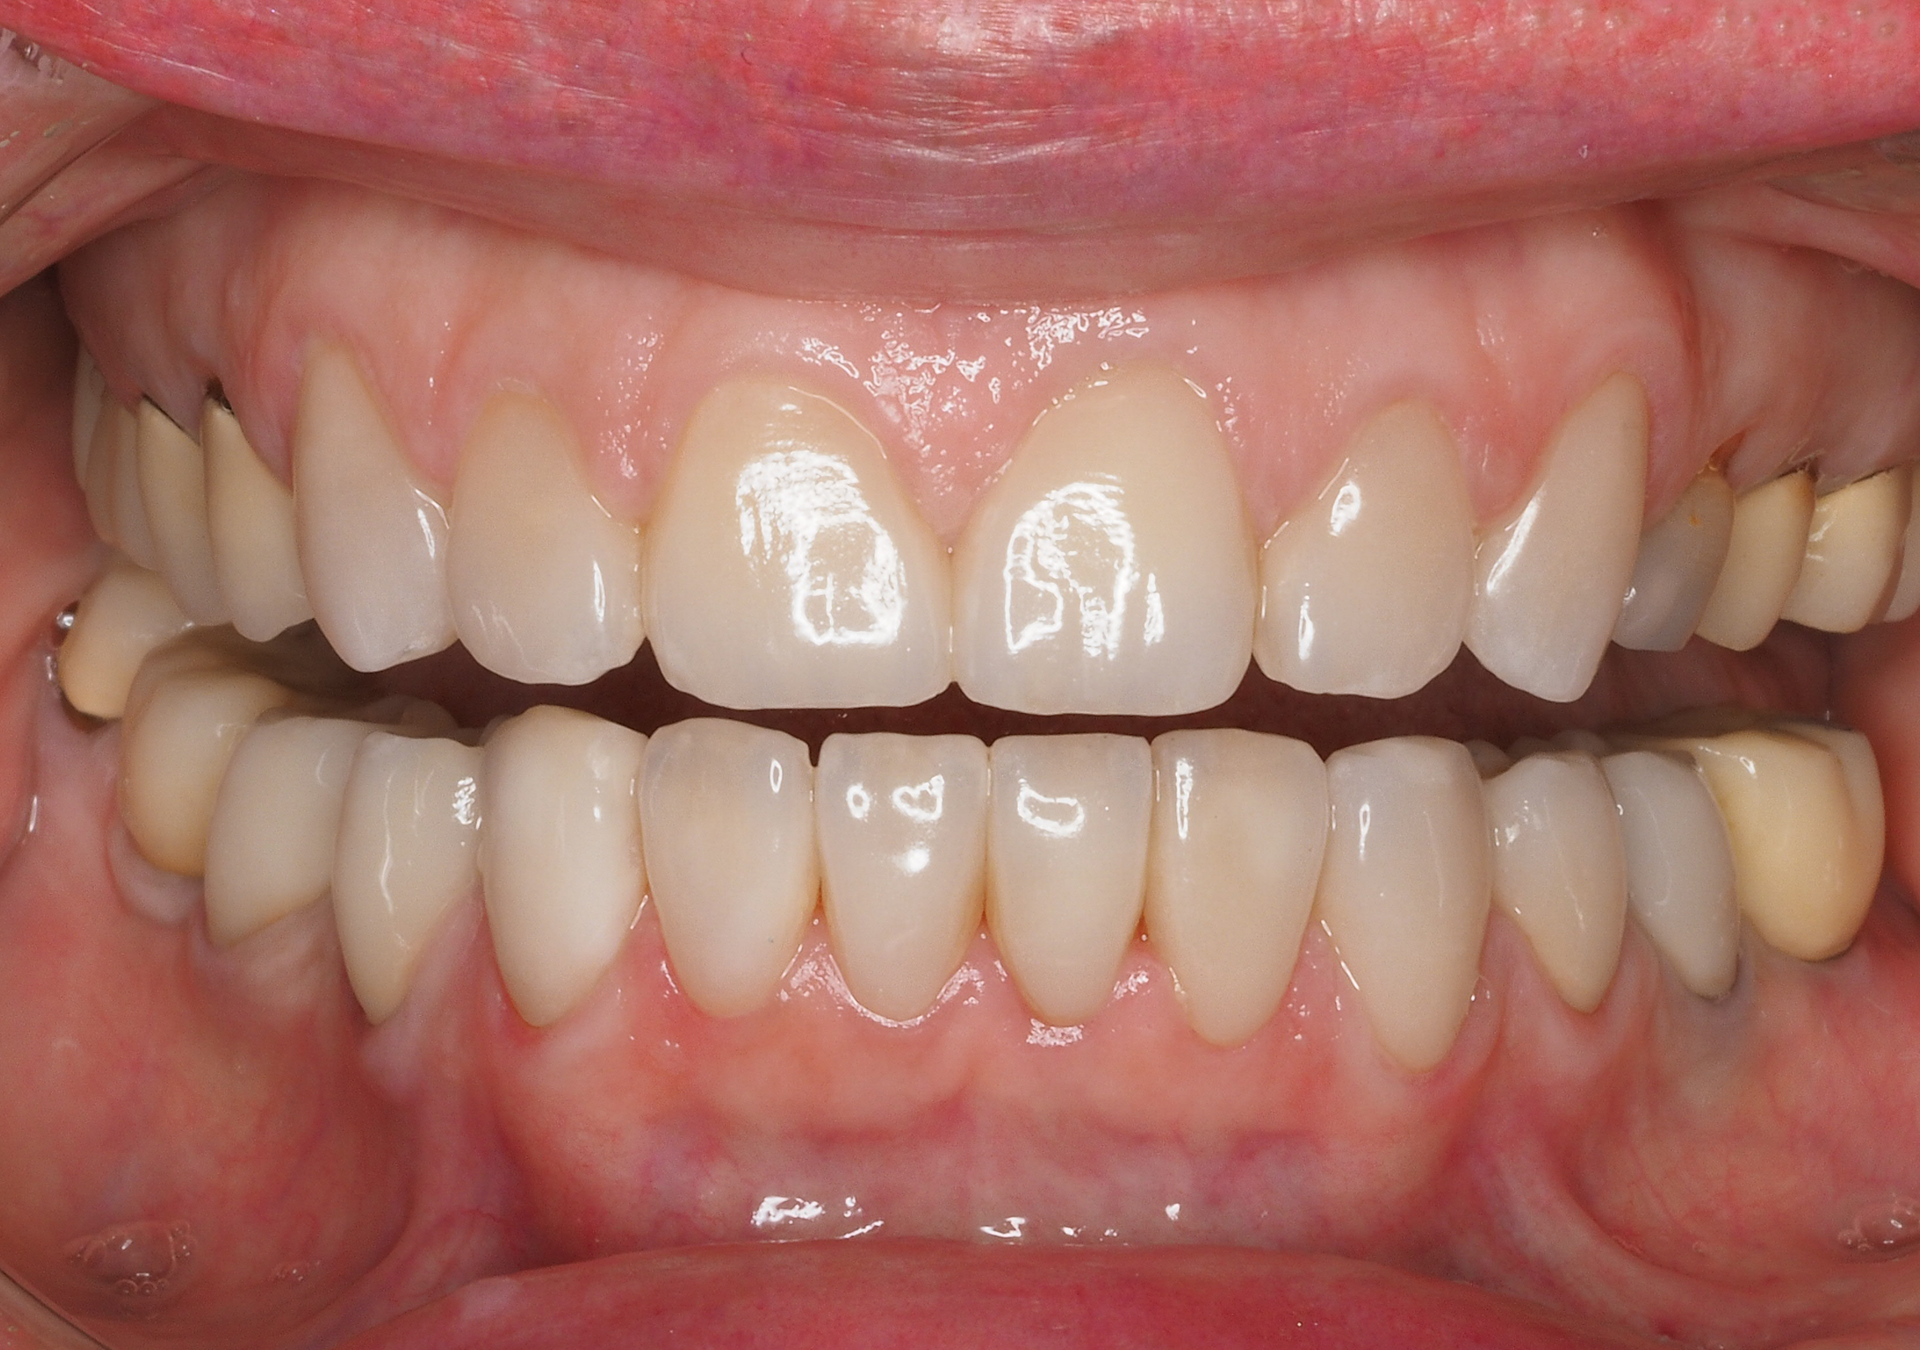

- Experiencia en la rehabilitación de casos complejos.

- Diseño de sonrisa y prueba estética previos para visualizar los resultados antes de iniciar el tratamiento.

- Coordinación con laboratorios de máximo nivel para lograr resultados estéticos y funcionales excelentes.